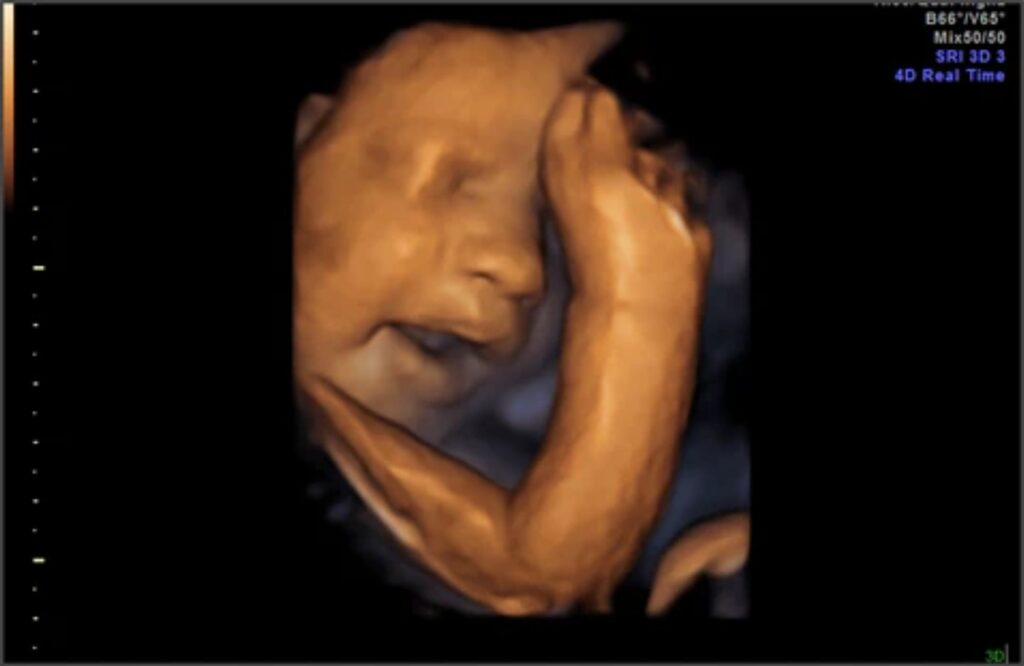

Bu haftada bebek ultrasonda daha hareketli görülür. Bunun sebebi ise bebeğin fiziksel olarak artık gelişmiş organlarının bulunmasıdır. Çünkü bu haftaya gelindiği zaman artık bebeğin boyu ve kilosu artmış, tüylenme başlamış, kafası ve kolları tam olarak belirgin olmuştur. Ama bu görüntüleri elde etmek biraz pahalı olduğu için her anne adayı buna başvuramaz ve diğer yöntemlerle çocuğun gelişimini takip etmeye çalışır.